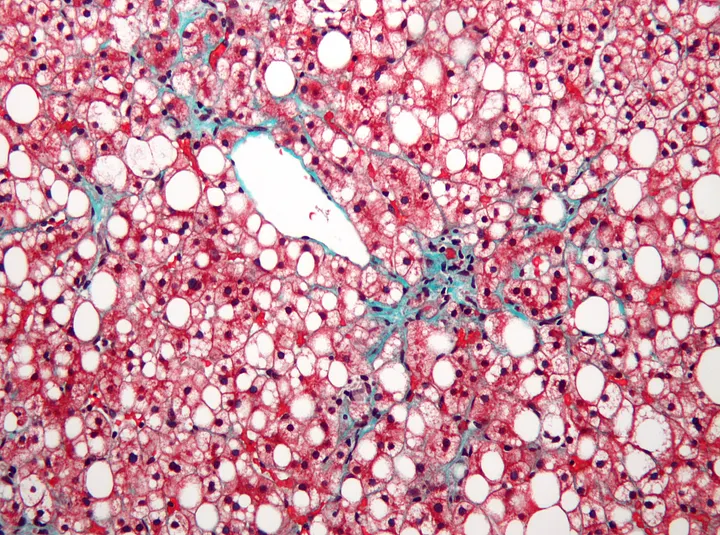

Um exemplar de seção transversal de um fígado humano sofrendo de doença hepática gordurosa não alcoólica. As manchas brancas são intrusões de gordura (Usuário do Wikimedia Nephron)